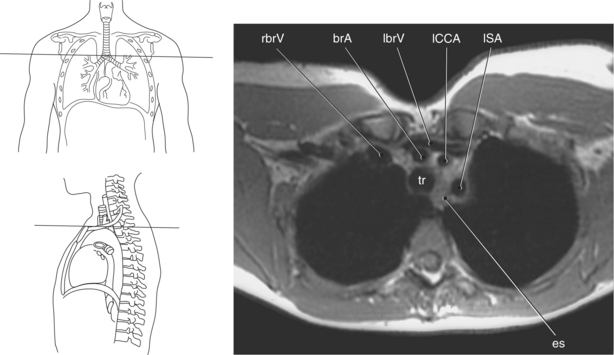

Blood travels to and from the heart through the great vessels, which include the aorta, pulmonary arteries and veins, and superior and inferior venae cavae (Figures 6.54 and 6.55). The aorta is the largest artery of the body and can be divided into the ascending aorta, aortic arch, and descending aorta. The ascending aorta begins at the base of the left ventricle at the level of the sternal angle, then curves superiorly and posteriorly as the aortic arch over the root of the left lung. The top of the aortic arch is approximately at T3 (Figures 6.56 and 6.57). The arch continues as the descending aorta posterior to the left bronchus and pulmonary trunk, on the left side of the vertebral body of T4 (Figures 6.58 and 6.59). The descending aorta passes slightly anterior and to the left of the vertebral column as it descends through the thoracic and abdominal cavities (Figure 6.60). While in the thoracic cavity, the descending aorta is commonly called the thoracic aorta, and while in the abdominal cavity, it is called the abdominal aorta. The pulmonary trunk is the origin of the right and left pulmonary arteries and lies entirely within the pericardial sac. It arises from the right ventricle and ascends in front of the ascending aorta, courses posteriorly and to the left, where it bifurcates at the level of the sternal angle (T4) into the right and left pulmonary arteries (Figures 6.61 through 6.63). The pulmonary trunk is attached to the aortic arch by a fibrous cord called the ligamentum arteriosum, the remnant of an important fetal blood vessel (ductus arteriosus) that links the pulmonary and systemic circuits during fetal development (Figures 6.54 and 6.61). The right pulmonary artery courses laterally, posterior to the ascending aorta and superior vena cava, and anterior to the esophagus and right mainstem bronchus, to the hilum of the right lung. At the root of the right lung, the right pulmonary artery divides into two branches, with the lower branch supplying the middle and inferior lobes and the upper branch supplying the superior lobe (Figures 6.61 through 6.64). The left pulmonary artery, shorter and smaller than the right, is also the most superior of the pulmonary vessels. It travels horizontally, arching over the left mainstem bronchus, and enters the hilum of the left lung just superior to the left mainstem bronchus (Figures 6.61 through 6.64). Within the lungs, each pulmonary artery descends posterolateral to the main bronchus and divides into lobar and segmental arteries, continuing to branch out and to follow along with the smallest divisions of the bronchial tree (Figures 6.61 and 6.64). Located inferior to the pulmonary arteries are the four pulmonary veins, two each (superior and inferior) extending from each lung to enter the left atrium (Figures 6.54, 6.55, 6.61, and 6.64 through 6.68). They commence in a capillary network along the walls of the alveoli, where they are continuous with the capillaries of the pulmonary arteries. The venous capillaries merge to form small vessels that unite successively to eventually form a single trunk for each lobe: three for the right and two for the left lung. Frequently the trunk from the middle lobe of the right lung unites with the trunk from the upper lobe, forming just two trunks on the right side prior to entering the left atrium. The right superior pulmonary vein collects blood from the upper lobe segments of the right lung and passes anterior and inferior to the right pulmonary artery, behind the superior vena cava. The right inferior pulmonary vein receives blood from the right lower lobes of the lung and crosses behind the right atrium to the left atrium (Figures 6.61 and 6.69 through 6.71). The left superior pulmonary vein receives blood from the left upper lobe of the left lung and courses anterior and inferior to the left main bronchus as it enters the left atrium. The left inferior pulmonary vein drains the inferior lobe of the left lung and passes toward the left atrium anterior to the bronchi (Figures 6.61 and 6.72 through 6.74). The pulmonary veins course more horizontally than the pulmonary arteries and are ultimately oriented toward the left atrium. At the root of the lungs, the pulmonary veins are anterior to the pulmonary arteries, which are anterior to the bronchus. While within the lungs, the branches of the pulmonary arteries are anterior to the bronchi, which are anterior to the pulmonary veins. The superior and inferior venae cavae are the largest veins of the body. The superior vena cava is formed by the junction of the brachiocephalic veins, posterior to the right first costal cartilage, and carries blood from the thorax, upper limbs, head, and neck (Figure 6.24). As it travels inferiorly, it is located posterior and lateral to the ascending aorta before entering the upper portion of the right atrium (Figures 6.54 through 6.59). The inferior vena cava is formed by the junction of the common iliac veins in the pelvis and ascends the abdomen to the right of the abdominal aorta and anterior to the vertebral column. It passes through the caval hiatus of the diaphragm and almost immediately enters the inferior portion of the right atrium (Figures 6.75 and 6.76).

The three main branches of the aortic arch are the brachiocephalic trunk, left common carotid artery, and left subclavian artery (Figure 6.84). The brachiocephalic (innominate) trunk is the first major vessel and the largest branch arising from the aortic arch. It ascends obliquely to the upper border of the right sternoclavicular joint, where it divides into the right common carotid and right subclavian arteries (Figures 6.85 and 6.86). The right common carotid artery ascends the neck lateral to the trachea to the level of C4, where it divides into the right external and internal carotid arteries. The right subclavian artery curves posterior to the clavicle into the axillary region, where it becomes the right axillary artery. The left common carotid artery is the second vessel to branch from the aortic arch. It arises just behind the left sternoclavicular joint and ascends into the neck along the left side of the trachea to the level of C4, where it bifurcates into the left external and internal carotid arteries. The left subclavian artery arises from the aortic arch posterior to the left common carotid artery and arches laterally toward the axilla in a manner similar to that of the right subclavian artery, where it continues as the left axillary artery (Figures 6.85 through 6.88). The right and left internal thoracic arteries arise from the respective subclavian artery at the base of the neck. They run deep to the ribs, just lateral to the sternum, to supply blood to the anterior portion of the thorax (Figure 6.89). The common carotid arteries supply blood to the head and neck, whereas the subclavian arteries supply blood to the upper extremities.